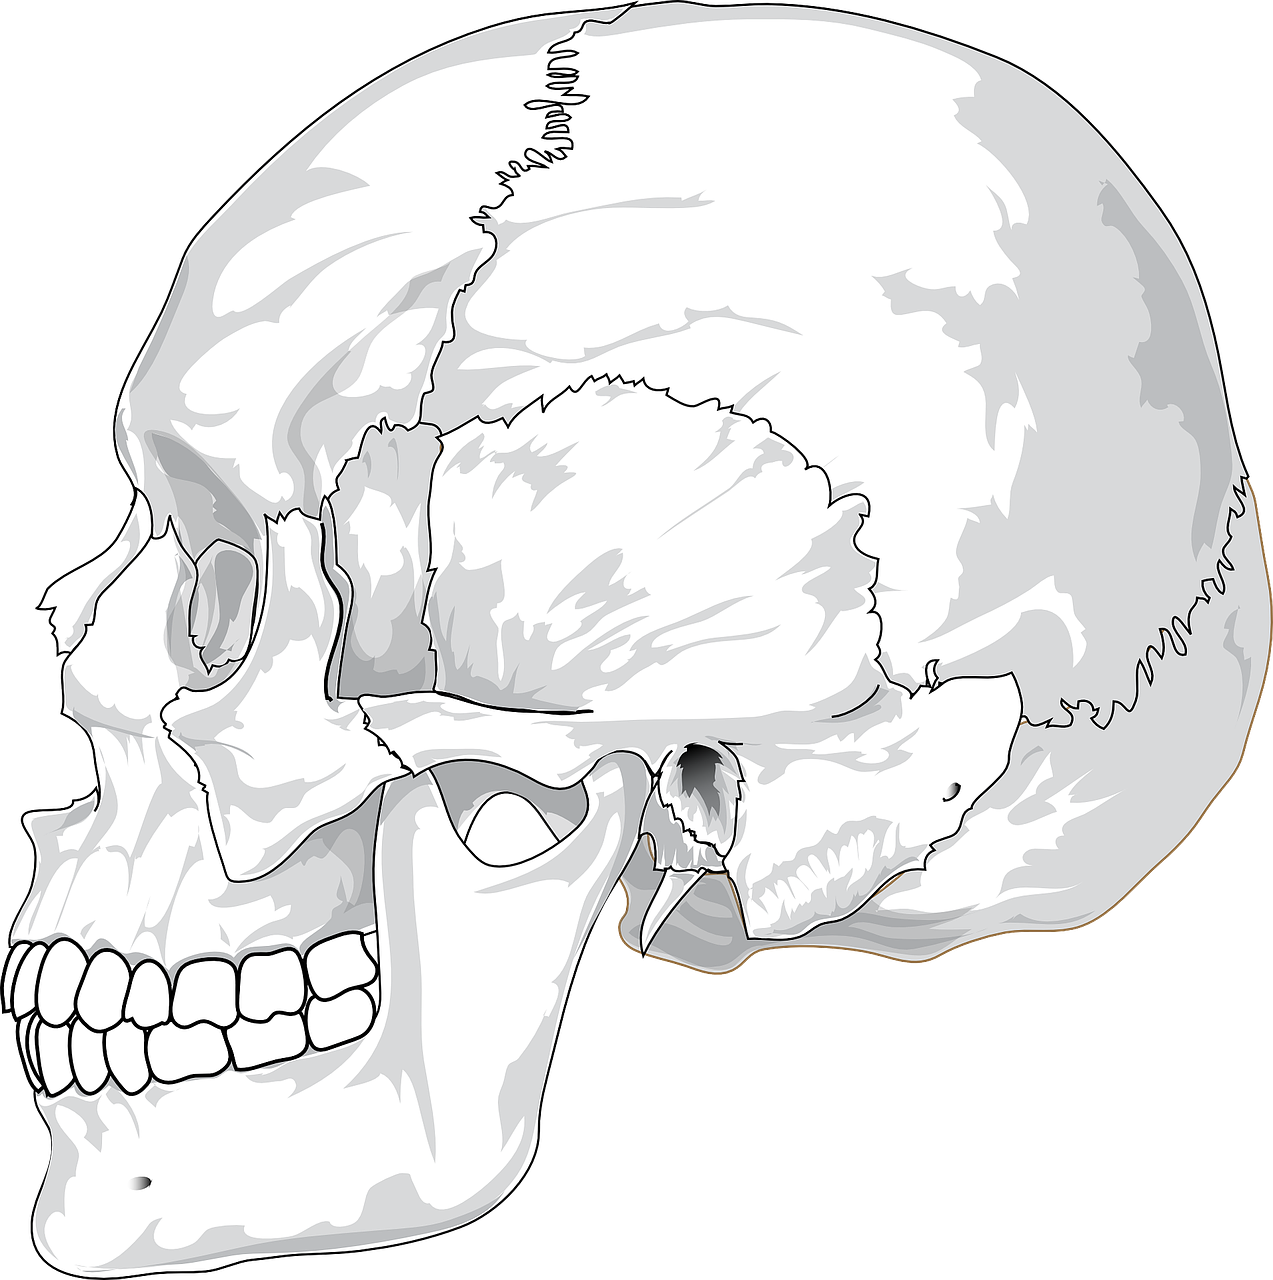

턱관절은 모든 턱운동의 중심축으로 작용하며 턱 근육과 인대에 의해 지지 되는데, 이때 턱관절 사이에 있는 디스크는 뼈와 뼈 사이의 쿠션 역할을 하게 되며 이러한 근육과 인대, 디스크, 턱뼈가 함께 어우러져 개구(입 벌리기)와, 저작(씹는 행위), 말하기, 삼키기 등의 복합적인 활동을 담당하게 되는데, 여러 요인에 의해 이러한 턱관절 기능에 이상이 생긴 것을 턱관절 장애 또는 악관절 장애라고 합니다.

턱관절 장애의 대표적인 증상으로 통증을 들 수 있는데, 음식을 씹거나 하품할 때 양쪽 귀 앞의 아래턱뼈와 저작 근육에 통증을 느끼게 되며 또한 입을 열 때마다 턱 관절에서 소리가 나며(관절 잡음), 입과 턱의 움직임이 제한되어 집니다(하악운동 제한).